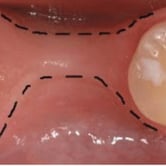

Pérdida de múltiples dientes

La pérdida de múltiples dientes es la ausencia de varios dientes que puede ser resultado de caries, enfermedades periodontales o traumatismos.

Los pacientes notan varios espacios vacíos en su boca, lo que afecta su capacidad para masticar y hablar adecuadamente.

El tratamiento incluye la colocación de varios implantes dentales para restaurar la función y la estética.